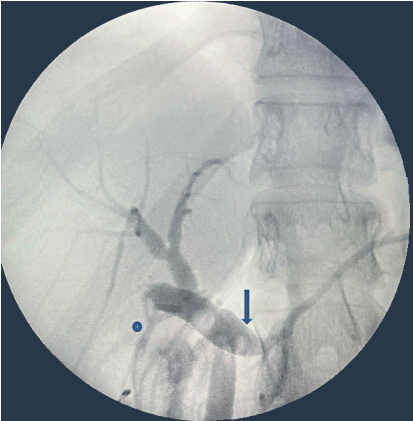

Se presentó el caso en junta multidisciplinaria y por la anatomía no clara se decidió realizar colangio pancreatografía retrograda endoscópica (CPRE) con fin diagnóstico. Se identificó una variación anatómica en la cual el conducto cístico drenaba en el conducto pancreático principal, denominada posible vesícula pancreática. Finalmente, se llevó a exploración quirúrgica por laparoscopia, se disecó el hilio hepático logrando ventana de seguridad de Straberg 10, pero con visualización de una estructura tubular de inserción baja al conducto cístico. Al realizar la colangiografía intraoperatoria no se logró aclarar adecuadamente la anatomía de la vía biliar, se identificaron dos conductos biliares distales, sin poder definir su terminación (Figura 3), por lo que se decidió convertir a cirugía abierta dada la complejidad del caso y la duda anatómica.

Figura 3. Colangiografía intraoperatoria donde se aprecia la vía biliar extrahepática dilatada, con aparente conducto cístico superpuesto (flecha), con terminación en el conducto pancreático, conducto hepático derecho accesorio (círculo azul) que desemboca en el cístico.